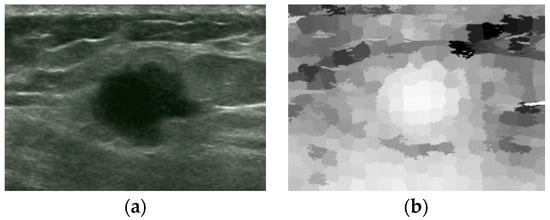

An Automatic Localization Algorithm for Ultrasound Breast Tumors Based on Human Visual Mechanism